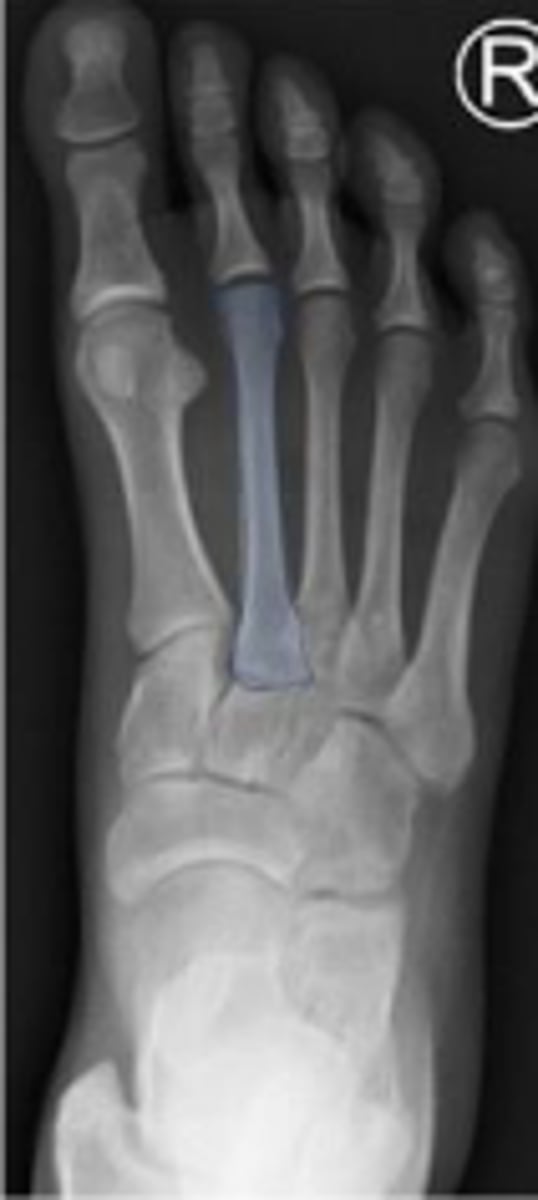

AP right foot

What is the name of the radiographic view?

Distal phalanx of the 1st digit of the right foot

Middle phalanx of the 2nd digit of the right foot

Cuboid of the right foot

Interphalangeal joint of the 1st toe of the right

foot

What joint is the arrow pointing to?

What is outlined?

2nd metatarsal of the right foot

Sesamoid bones of the right foot within the tendon of the flexor hallicus brevis

What are the arrows pointing to?

Medial sesamoid of the right foot within the tendon of the flexor hallicus brevis